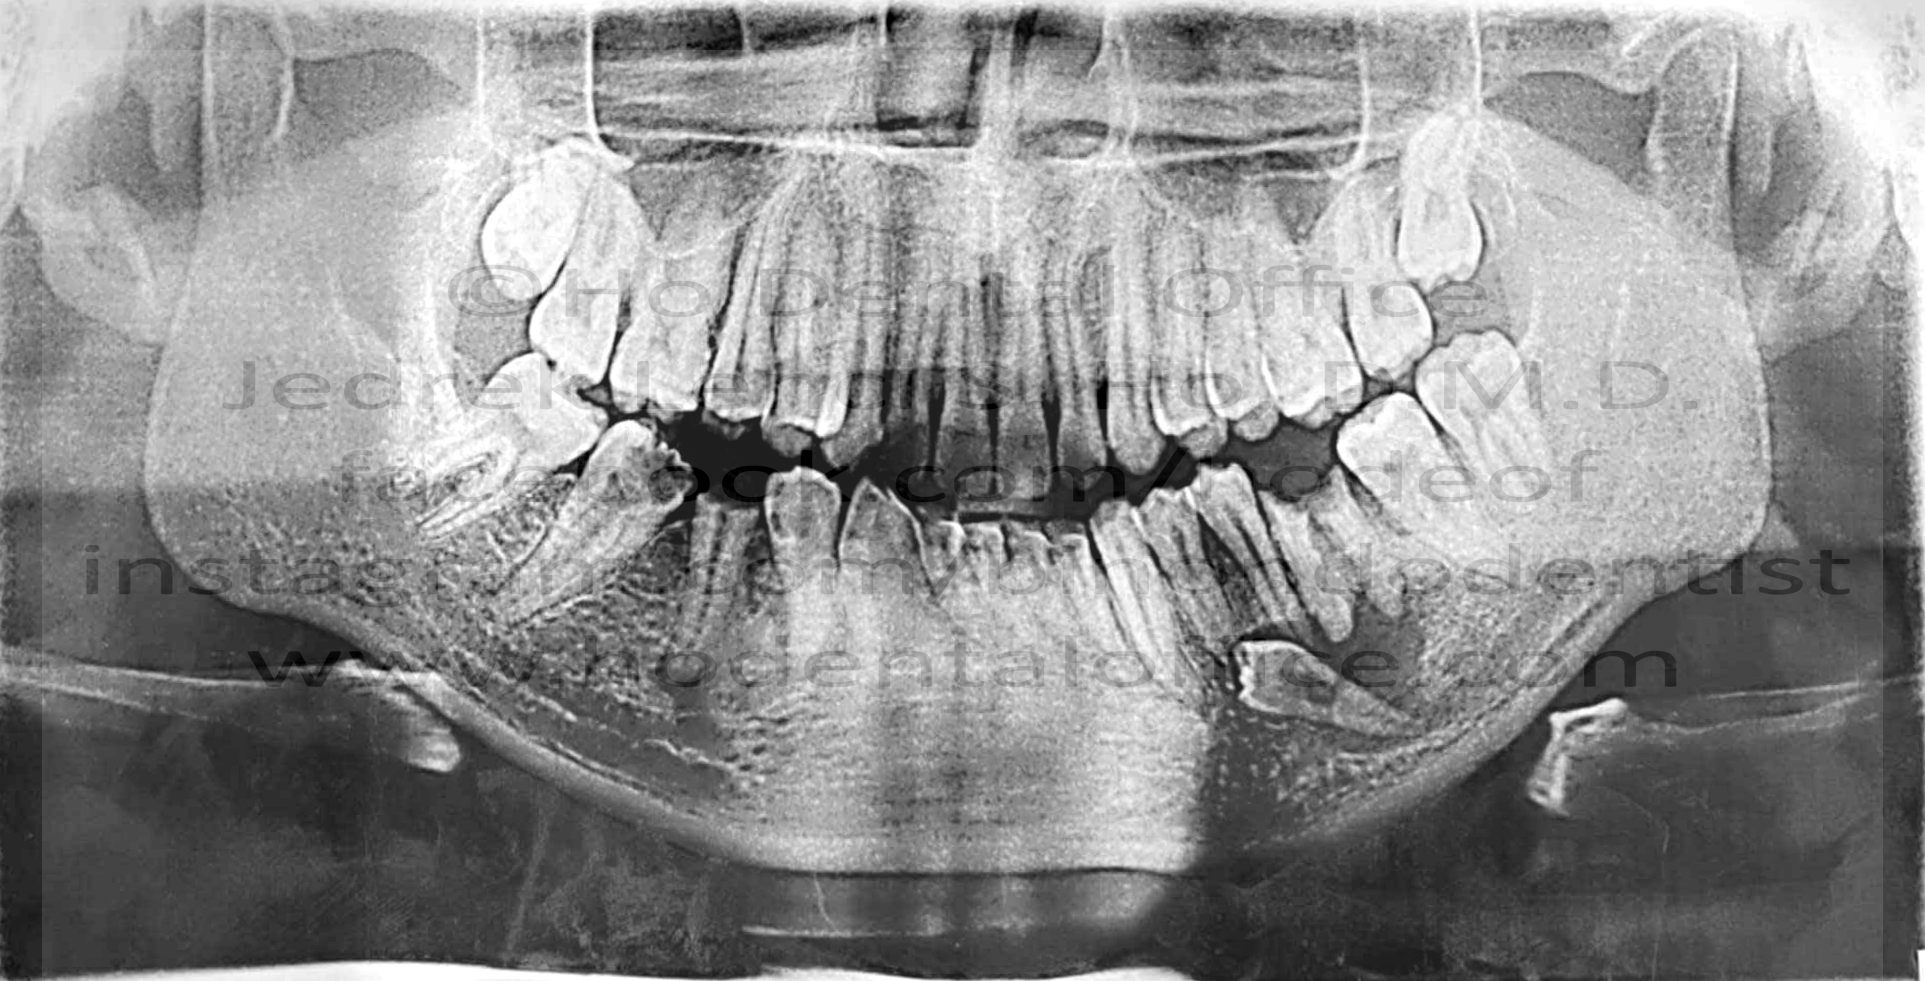

- prevention of difficult third molar extraction - Immature impacted third molars are easier to remove than fully grown ones! Third molars usually come out almost fully matured by the age of 18. Extracting it prior to that age would be easier since the tooth hasn't fully formed yet. Furthermore, the position of the third molar might transform to a more difficult position for extraction as the tooth matures and the patient ages.

![]() |